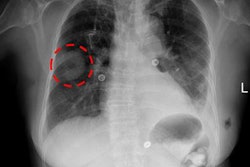

Above, eye-tracking scan path; below, heat map representing where observers looked. Images courtesy of Elizabeth Krupinski, PhD, Emory University.A wide variety of imaging perception studies are needed, and Wolfe offered up examples of the kinds of studies that qualify as imaging perception research:

- Another study idea involves eye-tracking in chest CT. Prior studies have looked at where the eyes go in the x- and y-axes -- left to right or up and down the 2D image. However, chest CT reading is performed on a stack of images in the x, y, and z planes, and 2D eye-tracking can't tell how deep in the stack the radiologist might be staring, or whether the reading patterns of novices and experts are similar.